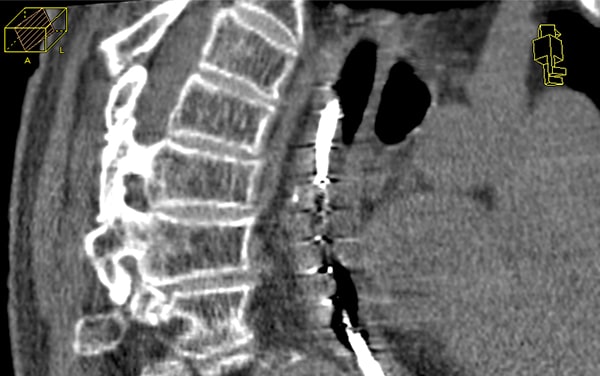

对于支气管和食道癌,此步骤并非必要步骤。在某些情况下,需要进行CT成像,用于制定治疗计划。对于食道癌,这可能是一个标准计划。

CT成像